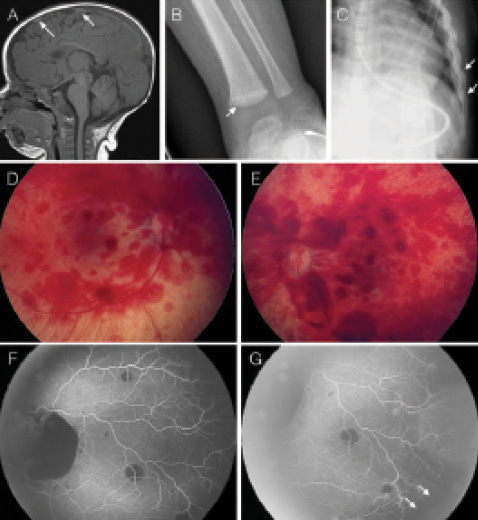

One high-yield concept for NEET-PG is Battered Baby Syndrome (Caffey's Syndrome). You'll often see a "discrepancy" between the history provided by the parents and the clinical findingsālike multiple fractures in different stages of healing.

Let's look at some of the classic radiological and physical signs of this syndrome.

This image is a perfect summary of the high-yield findings in child abuse. Notice the metaphyseal "corner" or "bucket-handle" fractures and the healing rib fracturesāthese are highly specific for non-accidental trauma.